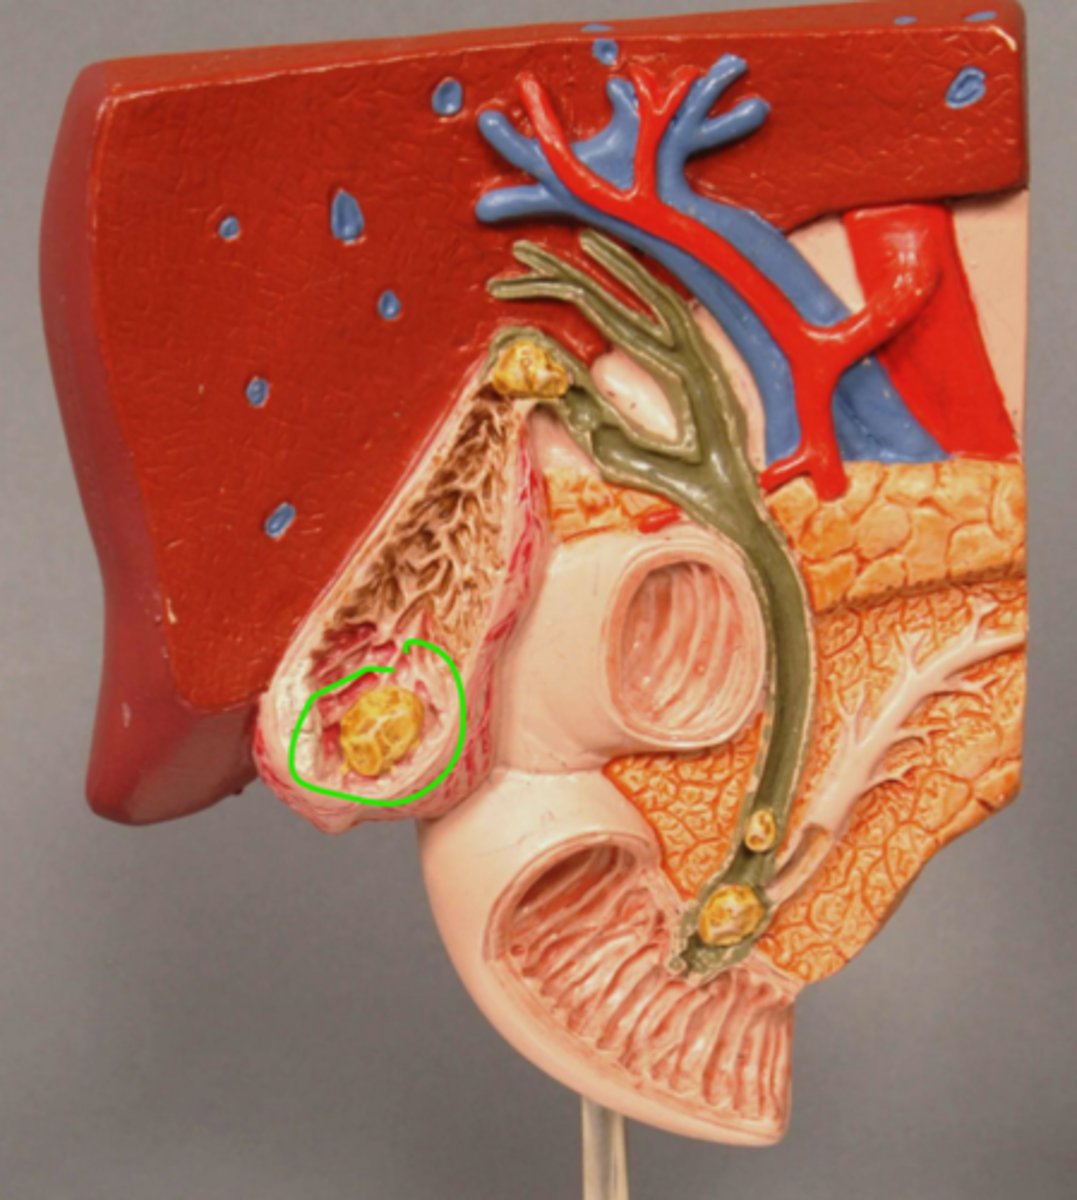

Gallstone in Fundus of Gallbladder

Gallstone at entrance to cystic duct

Acute Inflammation of Gallbladder (Cholecystitis)

Scarred wall of Gallbladder (Following Chronic Inflammation)